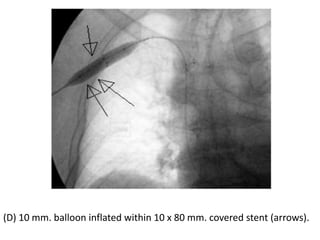

(D) 10 mm. balloon inflated within 10 x 80 mm. covered stent (arrows).

(E) Angiogram was done after deploying the stent, and showed partial

(D) 10 mm.balloon inflated within 10 x 80 mm. covered stent (arrows).

(E) Angiogram wasdone after deploying the stent, and showed partial opening of the central vein. Decision was done to put another stent in the axillary vein overlapping the proximal stent because there were some clots in that area.